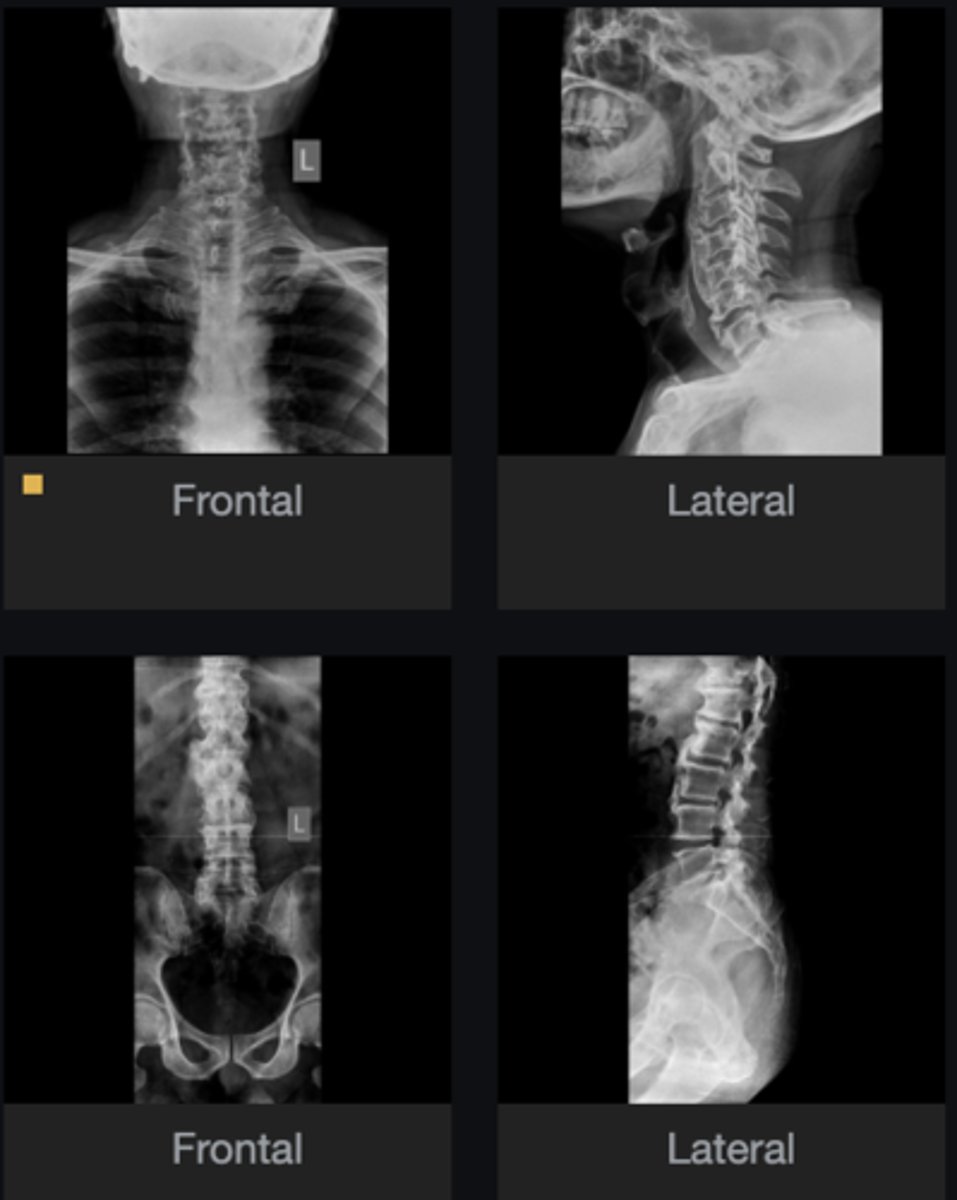

- Calcification of anterior longitudinal ligament

- Intercalary bone

- Preserved disc height across 4 levels

List at least 3 findings

Ossification of the posterior longitudinal ligament (OPLL)

What complication has occurred in the cervical spine?

Diffuse idiopathic skeletal hyperostosis (DISH)

Most likely diagnosis?

Neurosurgeon referral

Next step?

No

Would you adjust this patient?

What is the main finding on the CT study?

Would you adjust this patient's cervical spine?